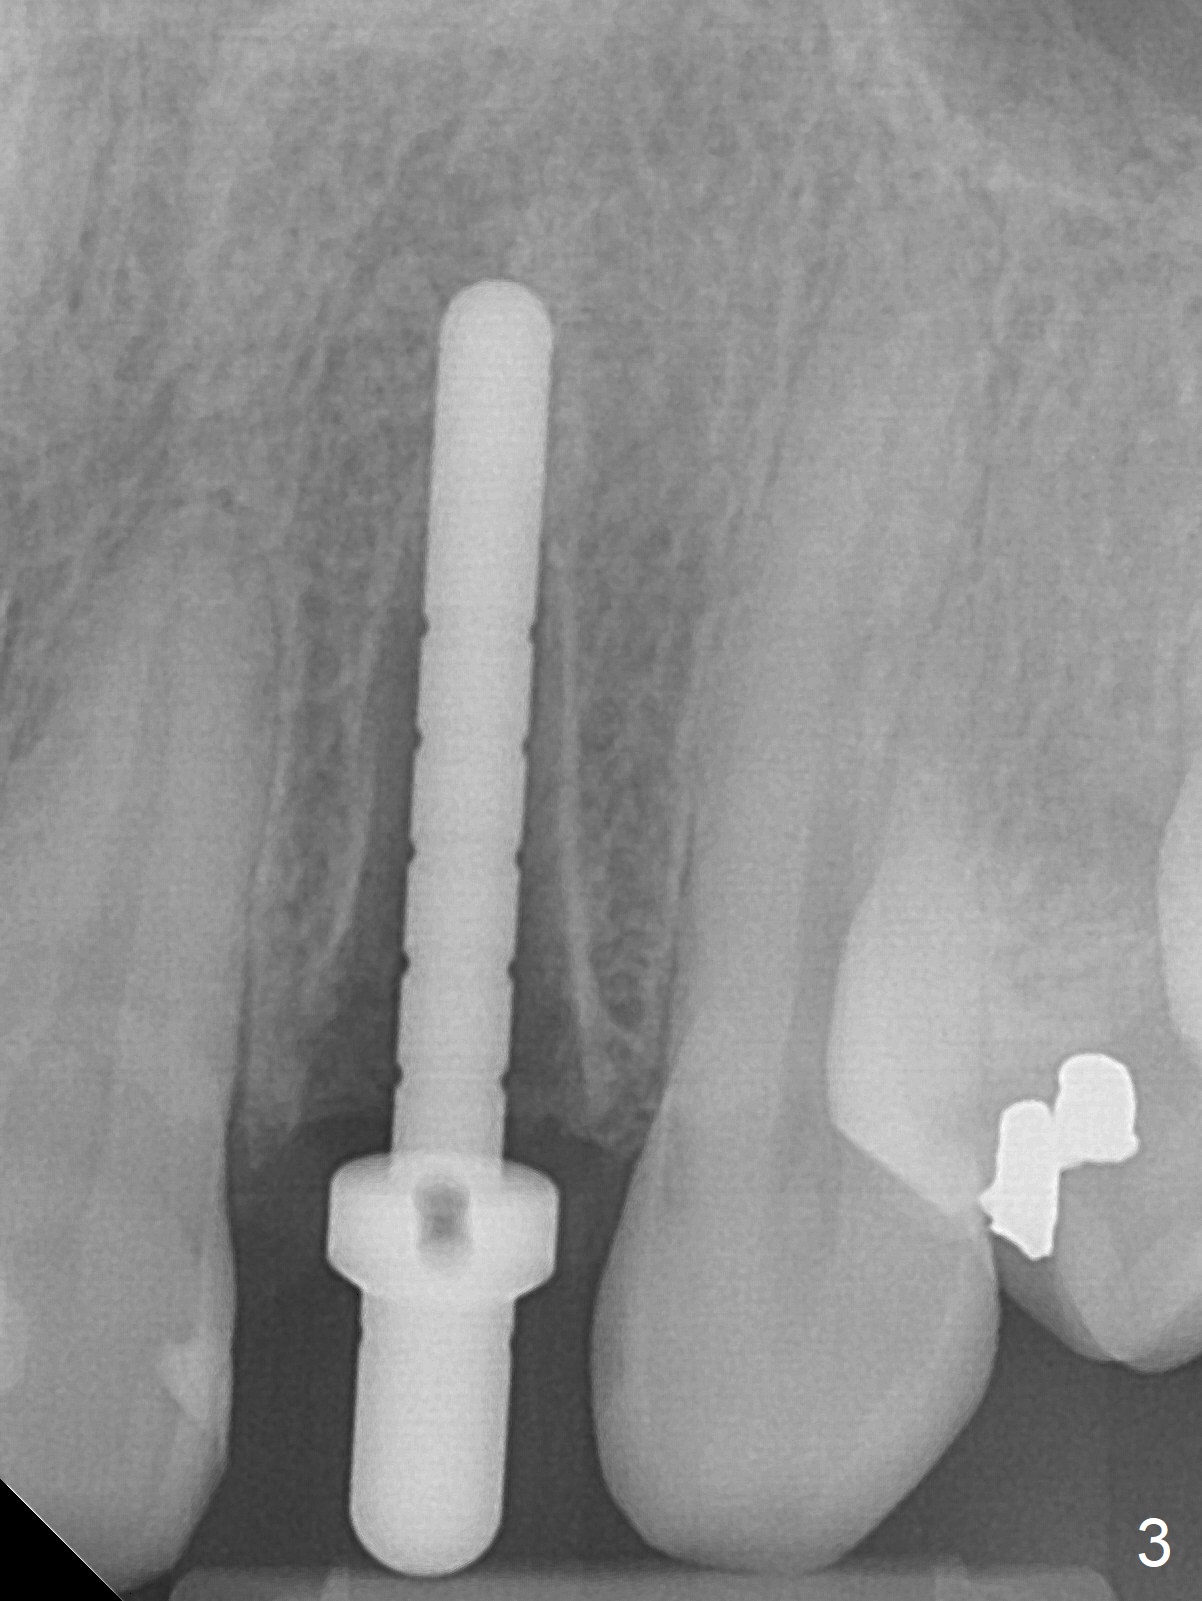

When the patient returns, the crown at #10 has displaced incisally (Fig.1,2 arrow). The initial depth is 15 mm (Fig.3, palatal gingival margin). After a 3.8x12 mm SM implant is placed (Fig.4), allograft is packed in the peri-implant space (*, as compared to Fig.3) and a 3.9x4(3) mm abutment is placed (A). More allograft is placed in the peri-abutment space (Fig.6 *). The existing crown (Fig.4,5 C) is hollowed, relined (R) and used as an immediate provisional (Fig.7-9). The patient is pleased with the appearance of the apically-repositioned provisional (Fig.7 arrow). She returns for impression 3.5 months postop (Fig.10). After change of abutment to 3.9x4(4.5) mm and new provisional, impression is retaken 5 months postop (Fig.11,12). It appears that the implant is palatally placed and a little large for the site (Fig.11 (B: buccal); Fig.12 (^: thin layer of the palatal plate)). If an angled abutment were used, a screw-retained crown might have been feasible. Due to the new provisional, the gingiva looks healthy when a permanent crown is cemented (Fig.13).